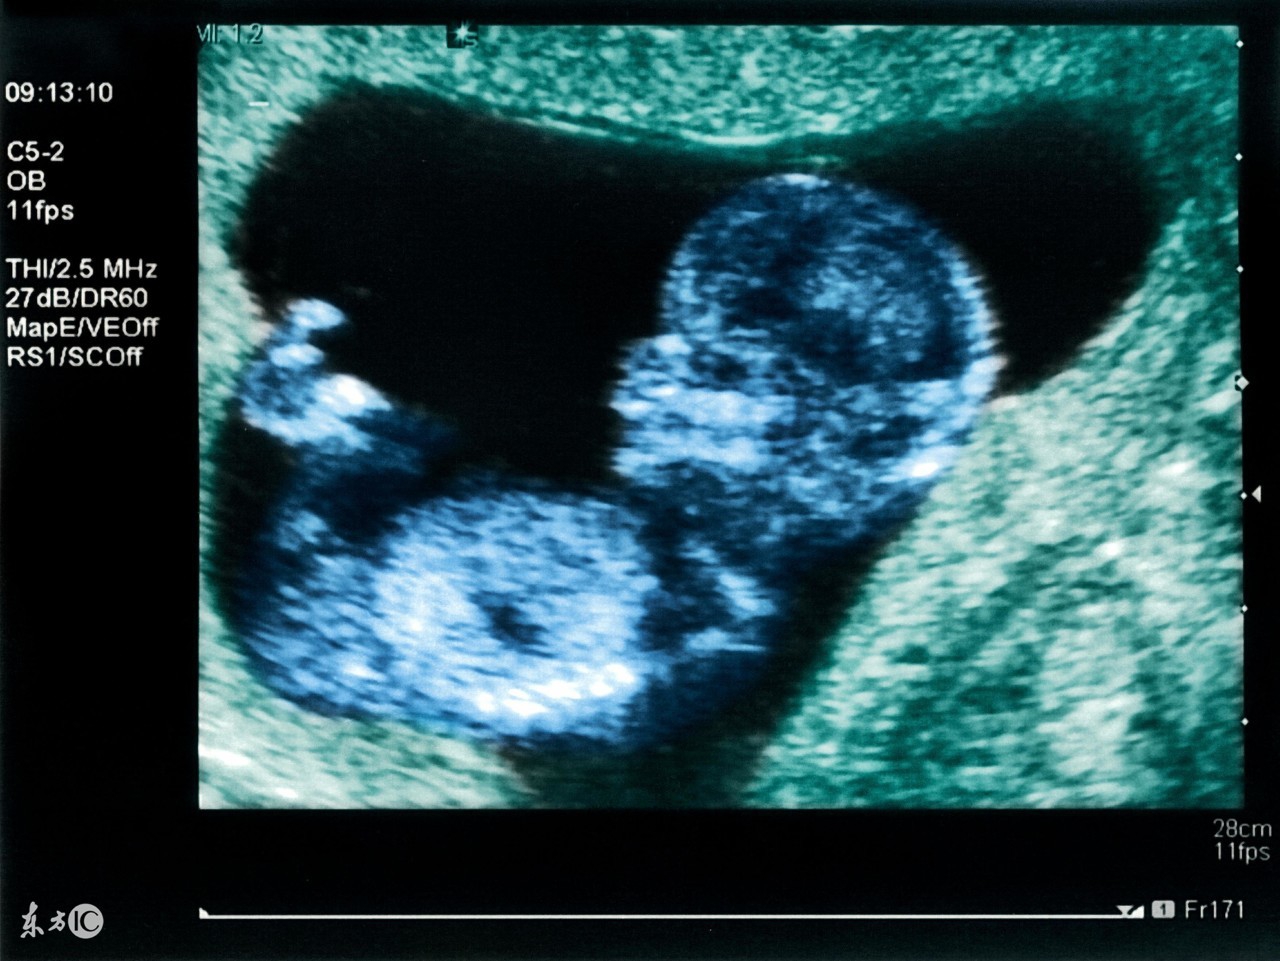

3.试管婴儿B超监测法。试管婴儿医院通过B超来监测排卵的方法较为准确,试管婴儿B超观察卵泡逐渐增大,在试管婴儿排卵日的前3天可达到19mm,试管婴儿准妈妈排卵当天会增大至20mm以上。观察日如果正好是试管婴儿排卵日,有时甚至可以在超声波上看到试管婴儿卵泡破裂。但是试管婴儿周期需要连续监测3-5次。